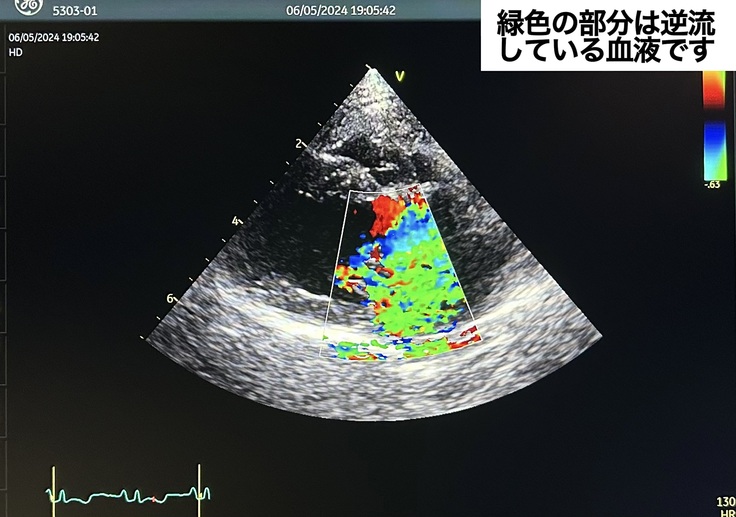

A院からご紹介いただいた心臓病専門のB院にて検査を受けました。

同日、B院から手術設備のあるC院へと繋いでいただき、C院で精密な検査をしていただきました。この時点で、2度目の肺水腫、余命数ヶ月、ステージDに近いC

もも子の心臓は血液を送る弁が切れたり伸び切っています。血液が逆流し、隣で寝ているとその音がシャーシャーと聞こえるほどです。いつ何があってもおかしくない状態です。